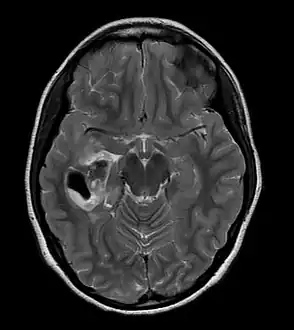

Pleomorphic xanthoastrocytoma (WHO grade II); Pleomorphic xanthoastrocytoma represents a distinctive glioma subtype -

PXA as visualized on an MRI -